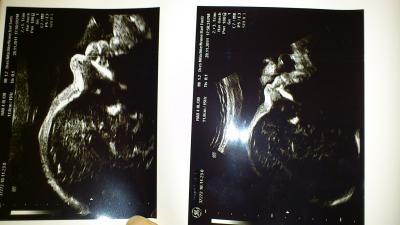

Hallo Mädels, mir is heut was passiert.... Kurz nach 18 uhr.....ich geh mit meinem mittleren und unserem Hund spazieren. Es ist dunkel...kein licht weit und breit....und dann passiert es....Mich legt es voll auf die Nase. Ich bin zwar auf die Knie und Ellenbogen gefallen aber der Bauch hat auch bissl abbekommen. Mein mittlerer gleich voll erschrocken und hst gleich nach dem baby gefragt. Wir nach hause.....ich zur vorsicht beim FA angerufen und geschildert was mir passiert ist. Die nette dame am Empfang sagt gleich das die babys gut geschützt sind aber bevor ich mir die ganze nacht Gedanken mache kann ich auch ruhig noch vorbei komm. Ich meine jungs gepackt und auf zum doc. Der hat mich dann auch gleich dran genommen. Und weil die jungs dabei waren auch nen us gemacht. Dem prinzen geht es gott sei dank gut!!! Da die plazenta an der hinterwand sitzt kann "der" auch nicht so schnell was passieren....und dann fragten meine jungs noch wie groß das baby jetzt ist. So um die 30 cm sagte der doc und dann wollten sie noch wissen ob es immer noch ein junge ist....und ja es bleibt dabei! Ich häng euch noch das us-bild mit an.... Liege jetzt auf der couch und tu heut nix mehr. Der kleine turnt gut rum....das ist ein gutes zeichen! Schön abend noch.... Lg Mandy

Bild zu Außerplanmäßig beim FA.... - Forum für Februar - Mamis